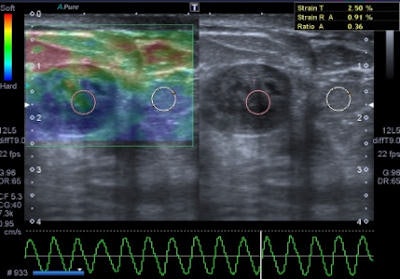

A 47-year-old woman with a small breast lump. Baseline ultrasound shows a hypoisoechoic nodule with regular and well-defined margins. Elastography demonstrates a pattern 2 according to the Ueno-Itoh classification with prevalent elasticity, as a predominance of green, with few, if any, blue and red spots inside. Strain ratio, measured by placing two different regions of interest (placed in normal breast tissue and within the nodule), was 0.36. Gross pathology confirmed a benign fibroadenoma. All images courtesy of Dr. Paolo Ricci.

Benign lesions are described at elastography as lesions with a low color map score (score 1-2), while the best cut-off point for discriminating benign from malignant masses falling at the 3-4 boundary of color map classification, according to the Ueno-Itoh score system. Cysts often appear as hard and low deformable lesions, commonly represented with a blue pattern at the color map and with a high strain ratio because of their low compressibility.

The elastographic properties of fibroadenomas are controversial, because some studies report a substantial difference of fibrotic components than surrounding parenchyma, while other authors describe fibroadenomas as difficult to evaluate by color map because of similar elasticity to the breast gland, the authors noted. Strain ratio range reported by most authors for this specific type of lesion is around 2.1 ± 0.8. Fibroadenomas with larger fibrotic component and poor cellularity can have a suspicious color map, but in all cases the strain ratio is lower than malignant forms, they added.